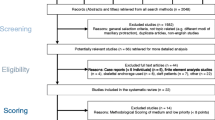

Thirty-one girls with Angle Class III malocclusion treated using a facial mask (FM group) and 11 girls with pseudo-Class III malocclusion (pseudo-III group) were examined. Lateral cephalograms at pre- and posttreatment were analyzed to evaluate maxillofacial changes. Cephalometric structural superimposition analysis originating with Björk and Skieller was also performed.

The ethics committee of the institution of the author’s affiliation approved all protocols in this retrospective study (approval no. 214). Subjects gave written informed consent for participation in this study.

The subjects consisted of 31 Japanese girls with Angle Class III malocclusion treated using a facial mask (FM group). Criteria for including an Angle Class III patient in the study were (1) overjet ≤ 0.0 mm; (2) Wits appraisal <− 2.0 mm; (3) Class III molar relationships; (4) retrognathic maxilla (point A to nasion perpendicular < 0.5 mm); and (5) age ≥ 6 years and ≤ 9 years at initial examination. Criteria for excluding a subject from the study were (1) presence of congenital anomalies, (2) history of trauma, and (3) previous orthodontic treatment.

The designs of the extra-oral facial mask and intra-oral appliance for the subjects were described in the previous study [18]. Briefly, bands were fitted on the maxillary permanent first molars or primary first molars for the intra-oral appliance. The extra-oral facial mask was a one-piece construction with an adjustable anterior wire and hooks. To avoid bite opening during repositioning of the maxilla, protraction elastics were attached near the maxillary canines with downward and forward pull of 30° to the occlusal plane. Mean treatment duration was 14 ± 4 months. Standardized lateral cephalograms were obtained before (T1; mean age, 8.0 ± 1.4 years) and after (T2; mean age, 9.2 ± 1.4 years) facial mask treatment from all subjects in the FM group.

Pseudo-Class III malocclusion is characterized by an anterior crossbite caused by a functional forward position of the mandible [7]. Another subjects consisted of 11 Japanese girls with pseudo-Class III malocclusion (pseudo-III group) were also examined. Inclusion and exclusion criteria for potential subjects in the pseudo-III group were the same as described in the previous study [18]. All subjects wore a lingual arch with spring [20] for improvement of the anterior crossbite by inclining the maxillary incisors labially. No subjects were treated using an orthopedic appliance. Standardized lateral cephalograms were obtained before treatment (T1; mean age, 8.1 ± 0.9 years) and during growth observation (T2; mean age, 9.4 ± 0.9 years) from all subjects in the pseudo-III group. Mean ages at T1 and T2 were almost the same for the FM and pseudo-III groups.

For all vectors and cephalometric measurements with significant differences in values between the FM and pseudo-III groups, the appropriate sample size was estimated at 6.18–26.11 (α (significance level of type I error) = 0.05, ß (significance level of type II error) = 0.20). The number of subjects in the FM and pseudo-III groups was 31 and 11, respectively, and was almost consistent with the proper sample size.